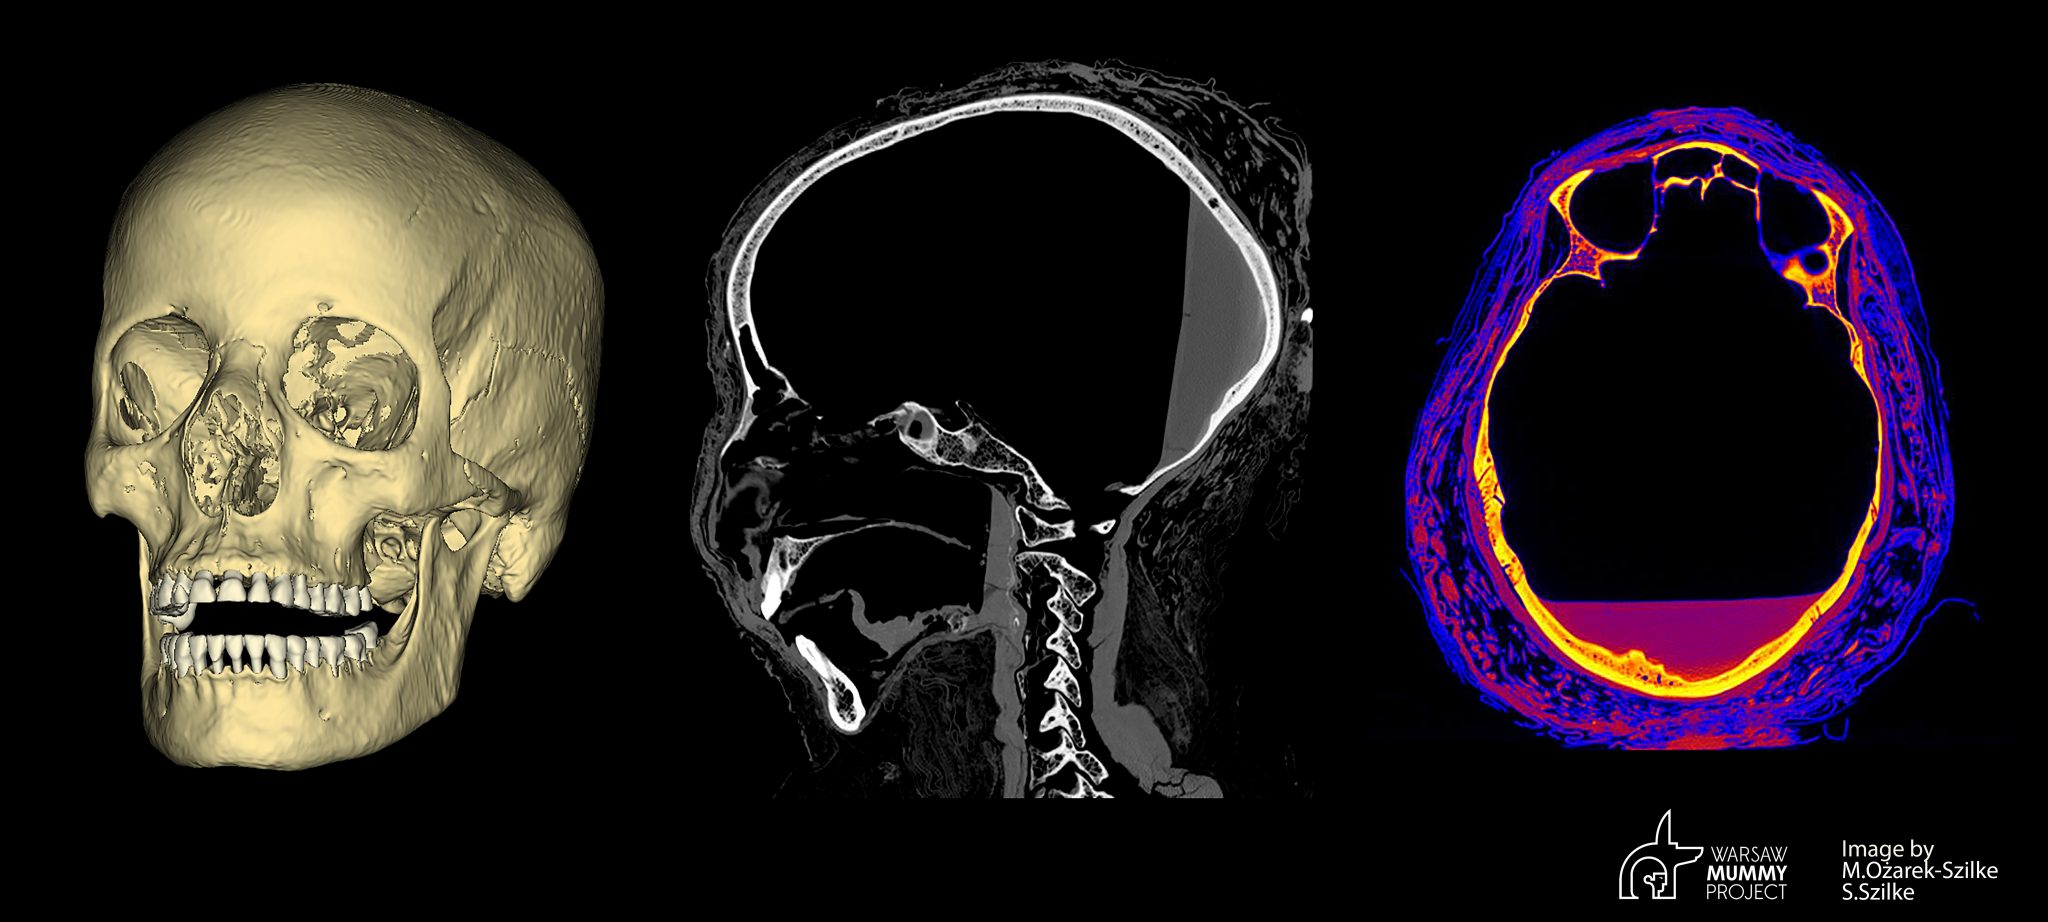

Los investigadores han descubierto que una momia de la colección del Museo Nacional de Varsovia, que es la única momia egipcia embarazada que se conoce, tiene grandes cavidades en la cara que no son típicas del proceso de momificación y que indican claramente que sufrió un cáncer nasofaríngeo.

“Al preparar el cráneo de la momia que examinamos para las impresiones en 3D, observamos grandes defectos en partes de los huesos faciales, más grandes que los que se suelen formar durante los procesos de momificación” – dijo Marzena Ożarek-Szilke, antropóloga y arqueóloga de la Universidad Médica de Varsovia (MUU). Según añadió, estas cavidades más pequeñas solían surgir cuando se extraía el cerebro a través de una de las fosas nasales. En ese momento, por ejemplo, se rompió el hueso etmoidal al “extraer” el cerebro.

“En primer lugar, hay cambios atípicos en los huesos de la nasofaringe que no son típicos del proceso de momificación, según los expertos en el estudio de las momias. En segundo lugar, las opiniones de los radiólogos basadas en la tomografía computarizada indican la posibilidad de cambios en los huesos debido a causas neoplásicas “- señaló el científico. Añadió que la poca edad del fallecido y la ausencia de cualquier otra causa de muerte pueden indicar muy probablemente “una causa oncológica”.